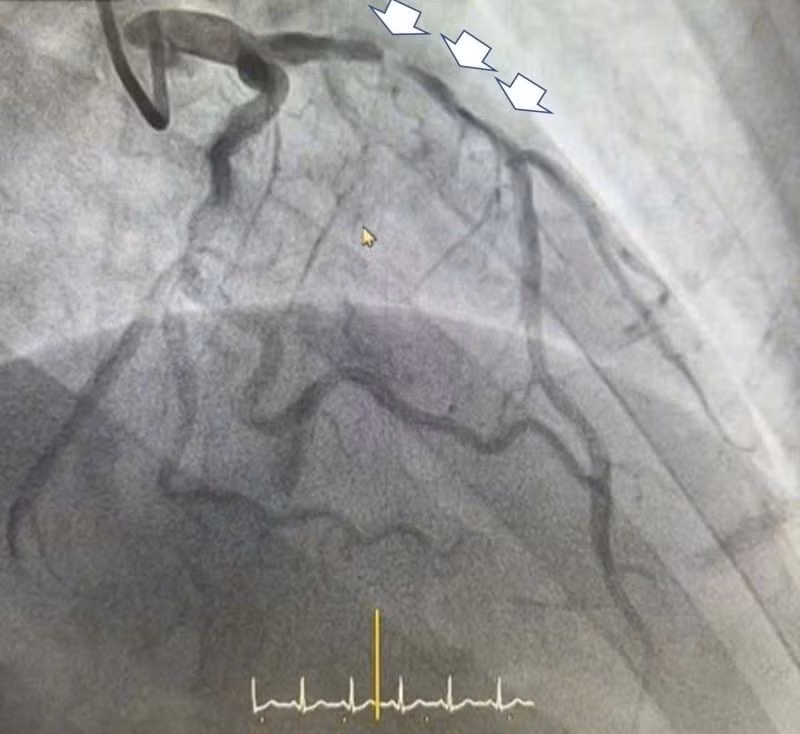

Tổn thương hẹp rất nặng - Ảnh BVCC

Kết quả chụp cho thấy bệnh nhân bị hẹp rất nặng động mạch liên thất trước và hẹp 80-90% động mạch vành phải, nguy cơ diễn tiến rất xấu nếu không được can thiệp kịp thời. Ngay lập tức, bệnh nhân được chỉ định đặt stent động mạch liên thất trước để tránh biến chứng nguy hiểm của nhồi máu cơ tim cấp.

BSCKII.BSNT Lê Đức Hiệp, khoa Tim mạch - Tim mạch can thiệp Bệnh viện Đa khoa Hồng Ngọc Phúc Trường Minh, cũng là người trực tiếp cùng ê kíp thực hiện ca can thiệp đặt stent cho anh H. cho biết: Động mạch liên thất trước của bệnh nhân bị hẹp rất nặng, nếu không can thiệp ngay có thể bệnh nhân sẽ đối diện với các biến cố thường gặp do nhồi máu cơ tim như suy tim nặng dẫn tới sốc tim, rối loạn nhịp thất nguy hiểm đe dọa trực tiếp đến tính mạng.

Rất nhanh chóng ê kíp đã can thiệp thành công và đặt 01 Stent có kích thước 3.5 x 38 mm, nhằm tái thông động mạch thủ phạm gây nhồi máu cơ tim cấp.

Trên phim chụp chúng tôi ghi nhận còn một tổn thương hẹp nặng khác, mức độ hẹp lên tới 90% ở động mạch vành phải, tuy nhiên đánh giá tổn thương, dòng chảy và tình trạng bệnh nhân, ê kíp đã quyết định sẽ can thiệp thì hai trong thời gian nằm viện để đảm bảo an toàn cho người bệnh.